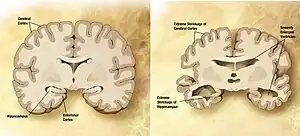

![]() Comparație între creierul normal (stânga) și creierul unei persoane cu Alzheimer (dreapta). Sunt evidențiate caracteristicile care le separă pe cele două. | |

La examenul macroscopic (cu ochiul liber) creierul arată o reducere accentuată a volumului, datorită atrofiei scoarței cerebrale (Atrofie corticală) cu micșorarea circumvoluțiilor cerebrale (pliurile creierului), predominant în regiunile frontală, parietală și temporală, lărgirii șanțurilor dintre circumvoluțiuni, a cisternelor cerebrale și a ventriculilor cerebrali (hidrocefalie externă și internă).

Secţiune frontală prin două creiere (Procesare computerizată a imaginii). Dreapta: Accentuată reducere de volum al creierului unui pacient cu boala Alzheimer. Stânga: Creier normal.